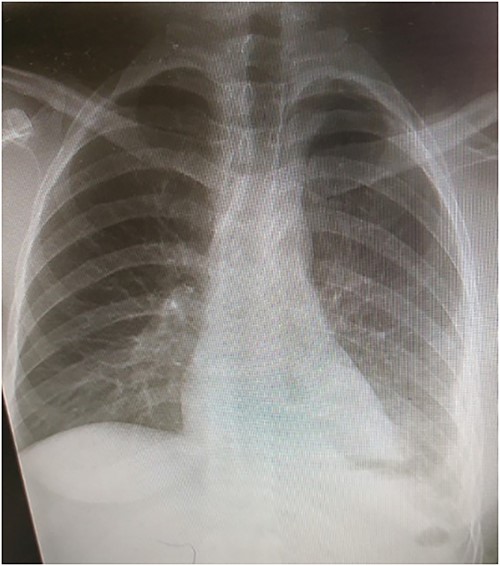

Laboratory tests showed white blood cells count of 9000/microliter with neutrophils 82%, mild anemia (Hb = 10 g/dl) and respiratory alkalosis (pH = 7.46, pCO2 = 28, and HCO3 = 20). Chest x-ray (CXR) of the chest was not able to visualize the left hemidiaphragm with a hollow viscus in the left thoracic cavity and a right shift of the mediastinum (Fig. 1). Computed tomography (CT) scan showed several viscera in the left thoracic cavity, containing air-fluid levels with the fluid not being homogeneous, pushing the left lung, the heart and the mediastinum to the right (Fig. 2). The CT also showed dilation of the esophagus with a presence of a fluid-gas level (Fig. 2). Additionally, there was atelectasis in the left lung. Finally, the liver and pancreas were in their normal position. An endoscopy was performed, which visualized the DH, which was 3 cm.

The patient was followed up with series of CXRs and patient is back to baseline (Fig. 5).